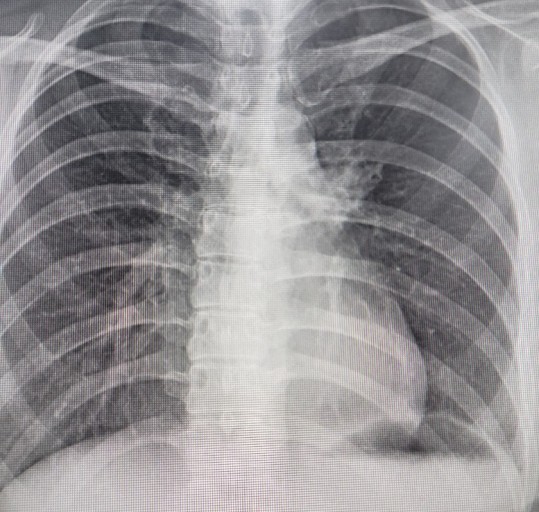

폐암 증상에는 기침, 체중 감소 흉통, 혈담 즉 피가 섞인 가래, 호흡곤란 등이 있지만, 위 증상은 다른 폐 질환에서도 나타날 수 있는 증상으로 구분하기가 어렵다. 그리고 폐암 초기에는 특별한 증상이 없는 경우가 대부분이라서 최근 흡연뿐 아니라 미세먼지 등 여러가지 요인으로 폐암이 발생하는 경우가 많아 정기검진으로 조기에 발견하는 것이 중요며 폐암 검진을 위해서는 특히나 저선량 흉부 CT를 촬영하는 것이 좋다라고 전문가들은 말하고 있습니다..

보통 숨소리는 크게 들리지 않지만, 목이나 폐 부분에 뭐가 걸린 느낌이 나듯이 숨소리가 거칠어지는 걸 느낍니다.면 폐에 문제가 생겼을 확률이 높다. 꼭 내원해 엑스레이를 촬영해 보는 게 바람직합니다..